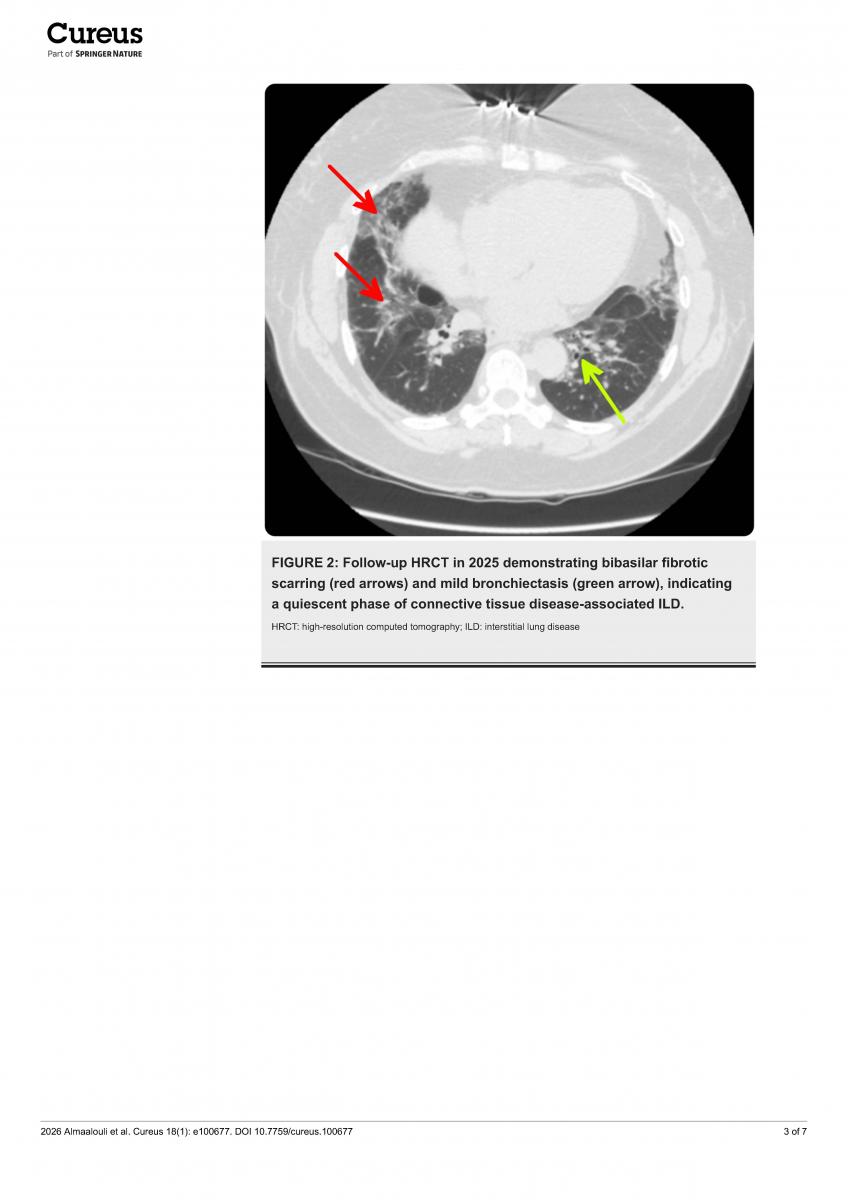

Antisynthetase syndrome (ASS) is a rare autoimmune inflammatory disease. Signs and symptoms include interstitial lung disease, myositis, Raynaud’s phenomenon, joint pain, "mechanic’s hands," and fever. Due to breathing difficulties, the disease is often misdiagnosed as idiopathic pulmonary fibrosis, and delays patients from receiving timely immunosuppressive treatment.